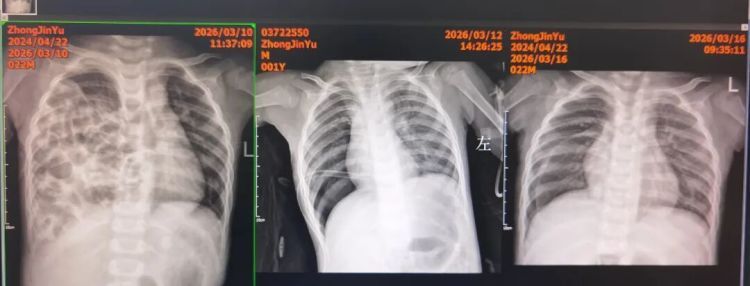

术后第四天,复查胸部DR:右侧膈肌完整恢复,右肺复张良好。拔除胸腔引流管后,孩子呼吸平稳,精神状态明显好转。不久前,小雨的检查报告显示其双肺复张良好,膈肌完整,小雨终于闯过了所有难关,顺利出院。

(从左至右)术前:右侧胸腔被肠管完全占据,纵隔移位,心脏偏左;

术后:膈肌恢复完整,右肺顺利复张,胸腔引流管位置良好;

拔管后复查:双肺复张理想,患儿呼吸功能快速改善。